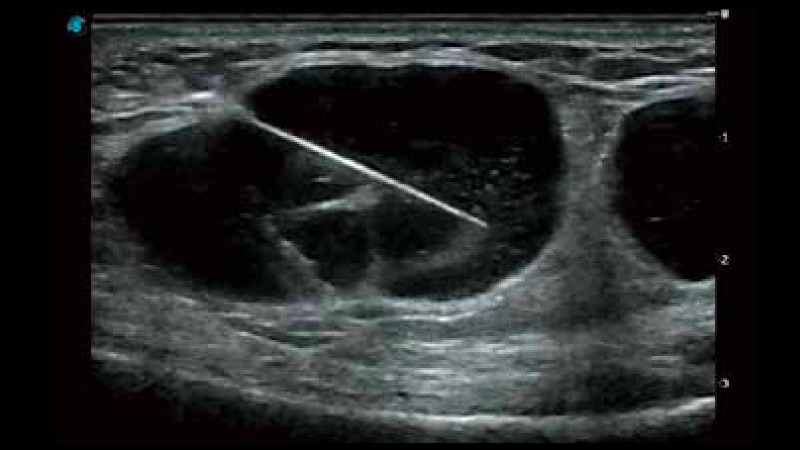

開立醫(yī)療通過不斷的技術(shù)創(chuàng)新,為大眾的生命健康提供持續(xù)關(guān)愛。P12 Plus采用全新一代超聲成像平臺(tái),新平臺(tái)旨在將真實(shí)還原組織解剖結(jié)構(gòu)作為首要目標(biāo)。平臺(tái)采用全新集成化硬件模塊,搭載新一代芯片,系統(tǒng)性能得到大幅提升,為您的診斷提供了豐富的臨床信息。優(yōu)異的圖像表現(xiàn),豐富的探頭配置,全面的應(yīng)用功能,為您日常診斷提供了可靠的助手。